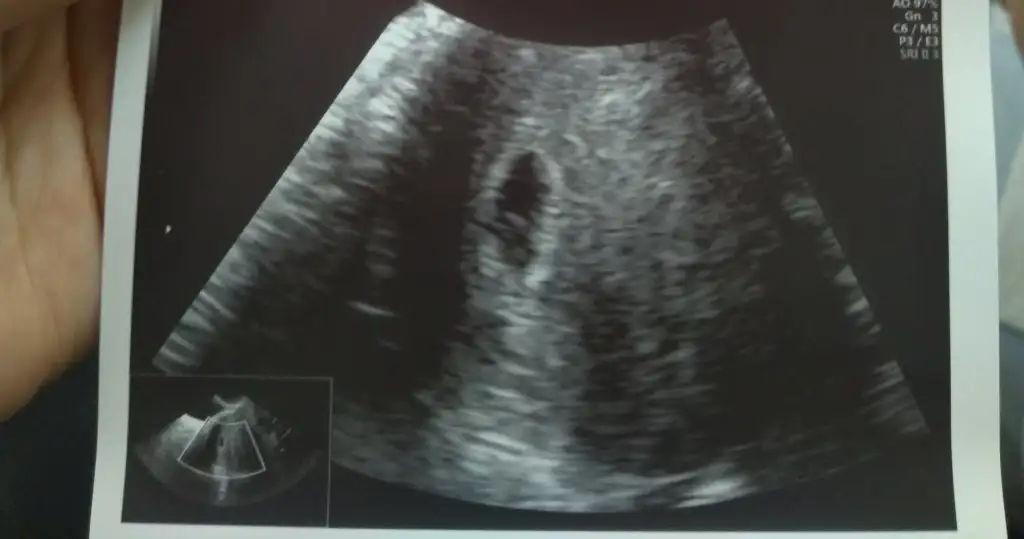

Transferimin 17.gününde kesemizi gördük çok şükürhaftaya kalp atışı için çağırdı doktor. Tam 5 haftalıkmış :))

Vajinal de gördü canım. Karından baksa görünmezdi daha beta 2800lerde. Ben vajinal muayene oldum gördü çok şükürBenim bebişler gözükmedi daha çok küçük dedi doktorSenin göründümüü

Görünürler canım keseden baska bişey görünmez bu zaman da zaten. Benm de sadece kese göründüAa çok iyiBen karından oldum sadece keseler gözüktü haftaya görürüöm inşallah